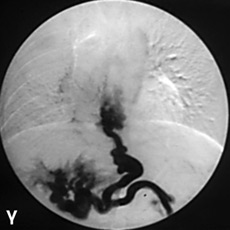

Η MRCP απεικονίζει με αρκετή ακρίβεια το χοληφόρο και παγκρεατικό δένδρο και

είναι εξέταση που προτιμάται σε παιδιά. Η ERCP είναι επεμβατική μέθοδος, προϋποθέτει

μεγάλη εμπειρία, ιδίως στην εφαρμογή της στα παιδιά και έχει αυξημένες πιθανότητες

επιπλοκών (αιμορραγίας ή παγκρεατίτιδας) (εικόνα 7).

EIKONA 7.

Πάγκρεας. MRCP. Κύστεις χοληδόχου και παγκρεατικού πόρου.

Πάγκρεας MRCP. Διάταση παγκρεατικού πόρου.

Πάγκρεας ERCP